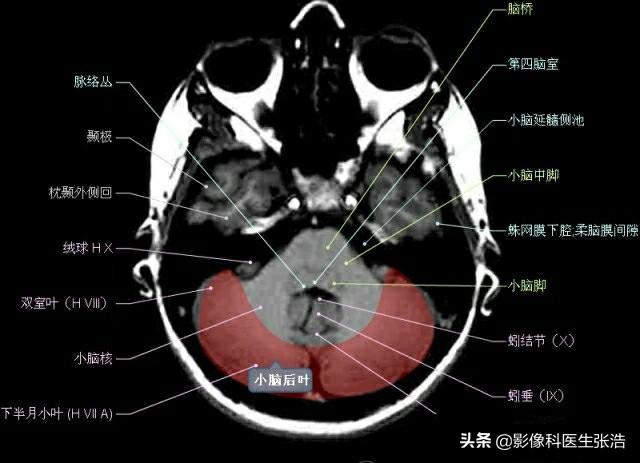

核磁共振(MRI)是一種利用磁場(chǎng)和射頻脈沖來(lái)生成身體內(nèi)部結(jié)構(gòu)的詳細(xì)圖像的非侵入性檢查技術(shù),頭部核磁共振主要用于檢查腦部疾病、神經(jīng)系統(tǒng)問(wèn)題以及血管狀況等,這項(xiàng)檢查對(duì)于疾病的早期發(fā)現(xiàn)和治療具有非常重要的意義。